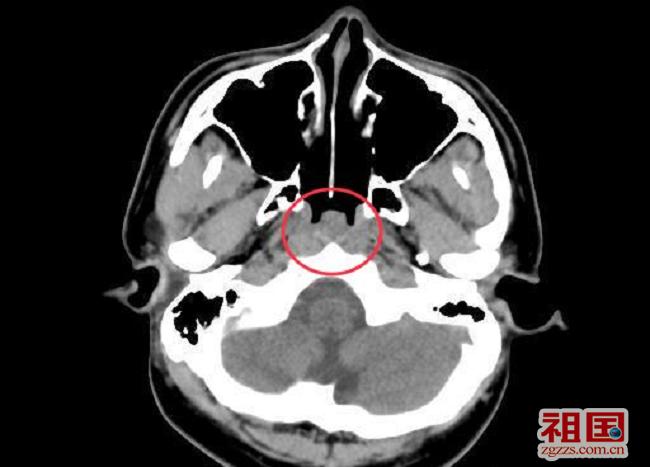

腺样体位置ct解剖图片,腺样体解剖位置示意图

儿童腺样体肥大影像表现及诊断标准

(红色圈圈内为肥大的腺样体)